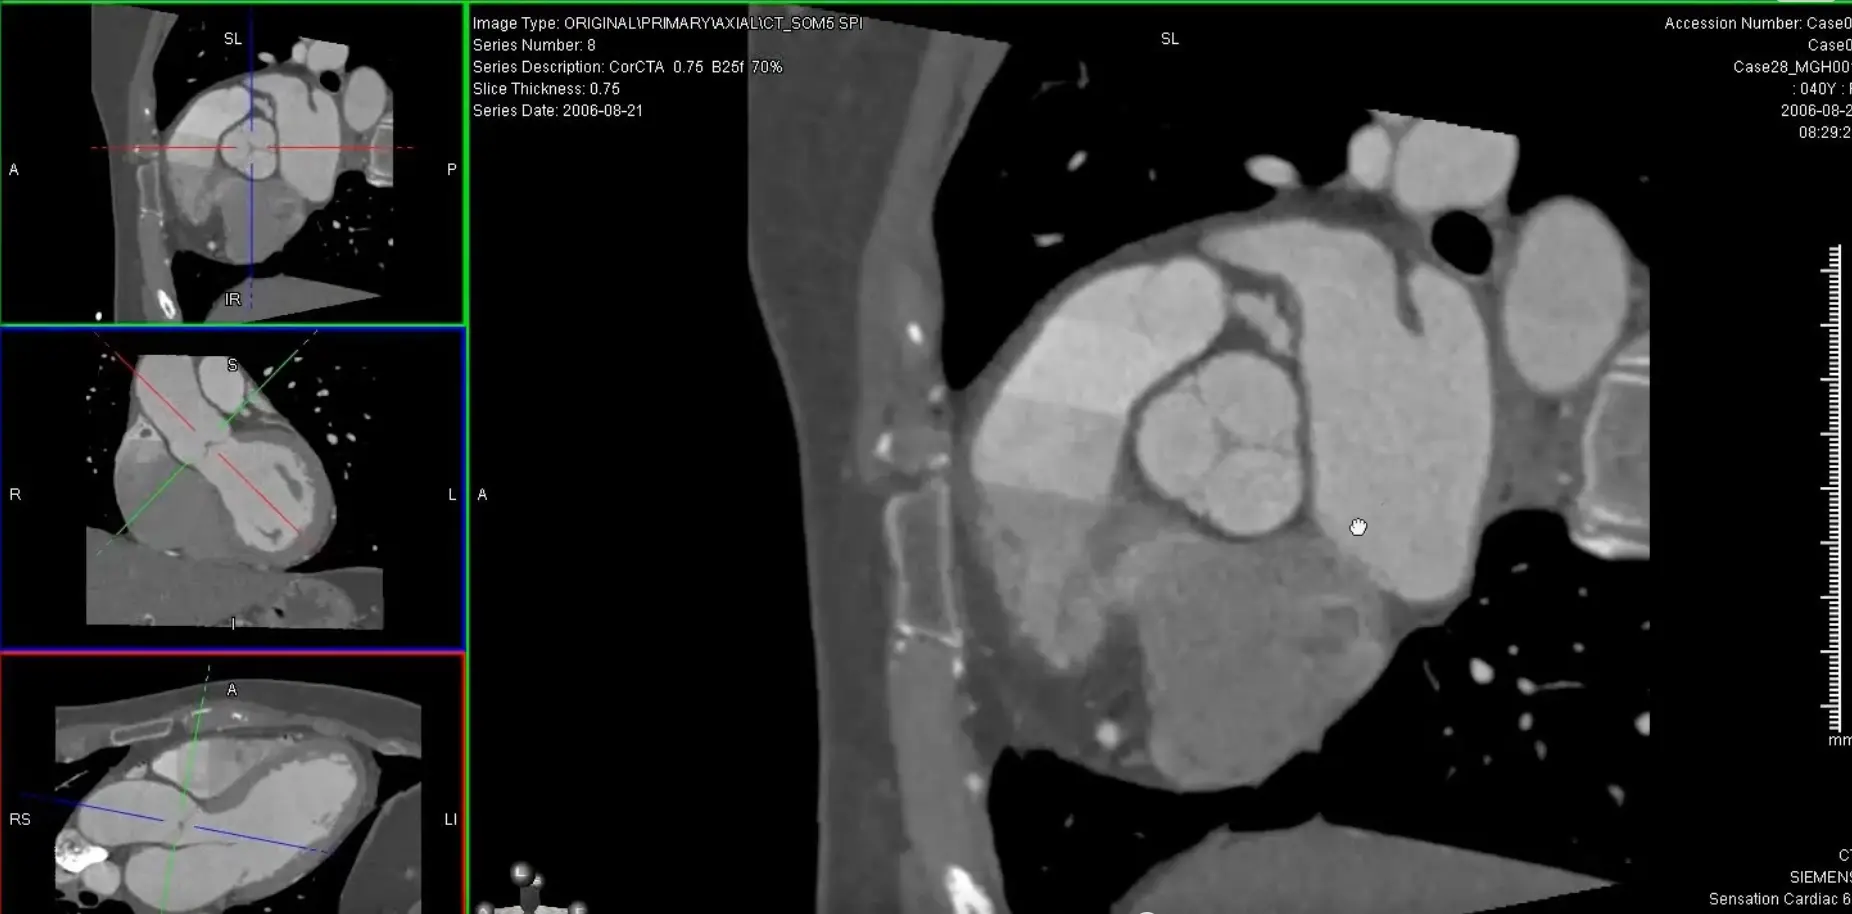

MPR of ‘C’ view of RCA

Above, but changed to MIP